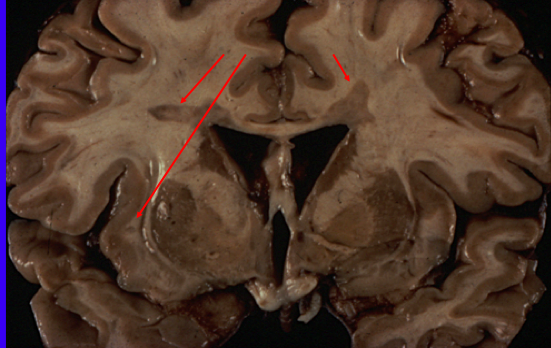

What are the red arrows pointing at?

The red arrows indicate MS plaques

Lesions of MS